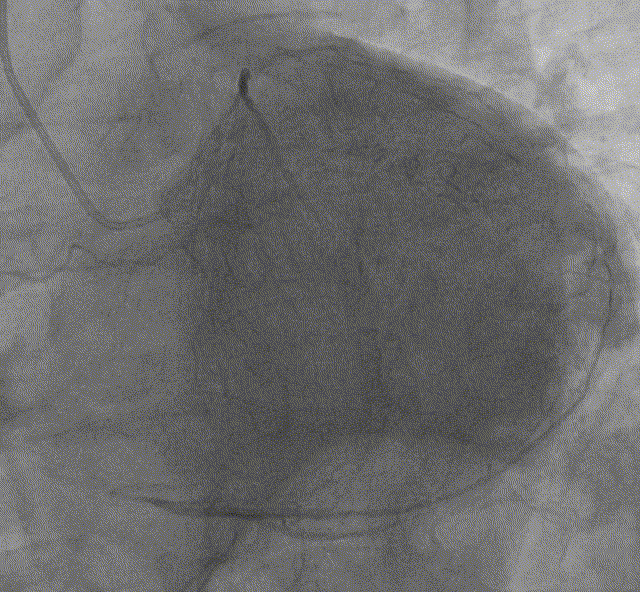

最终结果

Telescope™导引延长导管的应用体会

● 提供较好的额外支撑力,弥补指引导管支撑力不足,避免强支撑导管对冠脉口的损伤;

● 为迂曲、钙化病变,提供顺滑、可靠的输送平台,减少支架脱载的情况;

● 缩短手术时间,提高手术效率;

● 轻柔操作,缩短延长导管冠脉内停留时间,避免造成冠脉长时间缺血。